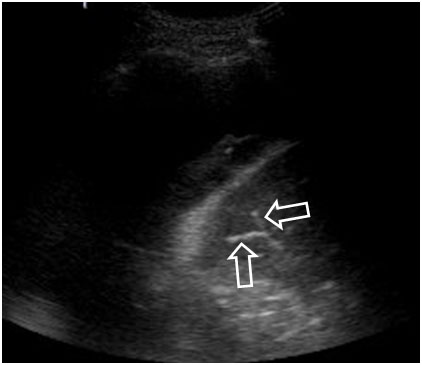

En la ecografía (signo del broncosonograma aéreo), el aire en los bronquios se ve hiperecogénico (flechas). Este caso corresponde a un colapso debido a un gran derrame pleural, que es la zona más oscura por encima y a la izquierda del pulmón.